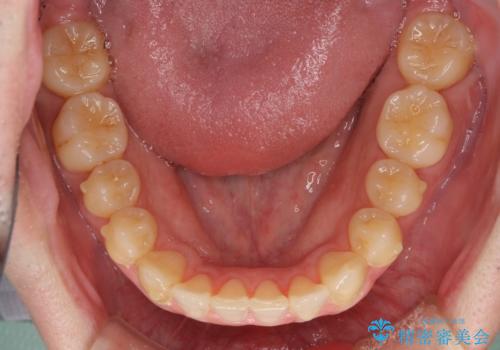

前歯のクロスバイト インビザラインによる矯正治療

- 上下のクロスバイトと前歯のデコボコを気にして来院された患者様です。

インビザラインを用い、IPR(歯と歯の間を削る)と歯列全体を拡大させることで、歯並びを整えていくこととしました。

上下ともに歯列全体を後方に移動させるため、上下の親知らずを抜歯することとしました。